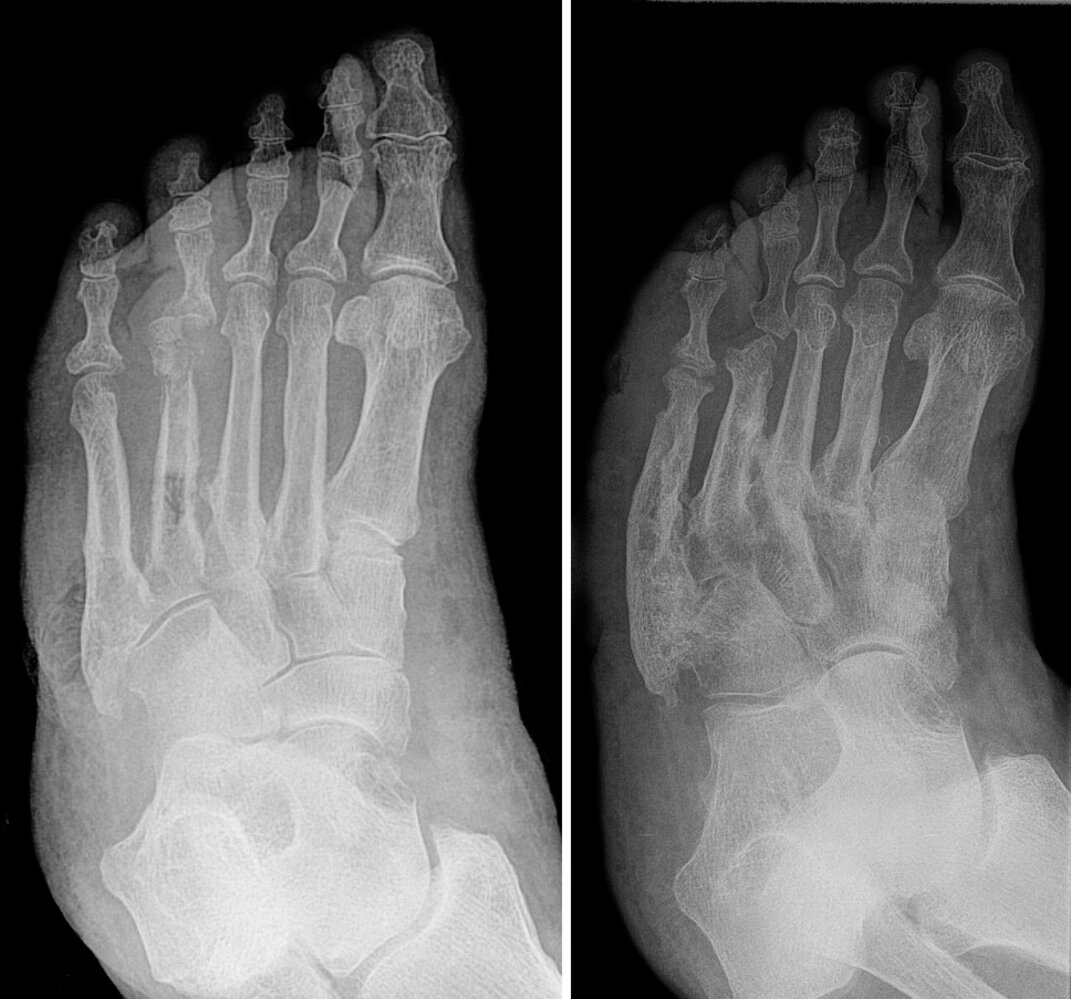

Diabetic foot osteomyelitis [3][10]

• Common in patients with malum perforans ulcers

• Osteomyelitis should be suspected in any patient with an ulcer and any of the following features: [3][11]

• Clinical features of skin and soft tissue infection (e.g., erythema, edema)

• Ulcer size > 2 cm2 and/or ulcer depth > 3 mm [8]

• Exposed bone tissue

• Positive probe-to-bone test

• A clinical test to evaluate for osteomyelitis related to chronic ulcers

• A sterile blunt probe is inserted into the ulcer; direct contact of the probe with the bone indicates potential underlying osteomyelitis.

• Chronic (lasting several weeks) and/or treatment-resistant ulcers

• An ulcer overlying a bony prominence

• Markedly increased ESR (> 70 mm/hour)

• Unexplained leukocytosis

• Obtain serial plain radiographs and/or MRI (see also ā€œDiagnostics of osteomyelitisā€). [3]

• Treatment involves optimizing the management of diabetes, antibiotics, and possible surgery (see ā€œTreatment of osteomyelitisā€). [3]